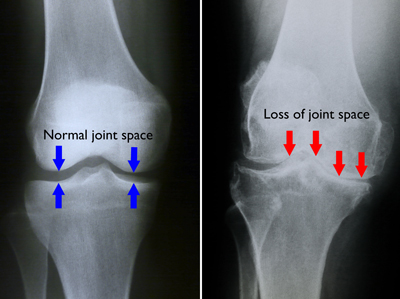

(Left) Normal joint space between the femur and the tibia. (Right) Decreased joint space due to damaged cartilage and bone spurs.

(Left) In this x-ray of a normal knee, the space between the bones indicates healthy cartilage (arrows). (Right) This x-ray of an arthritic knee shows severe loss of joint space.